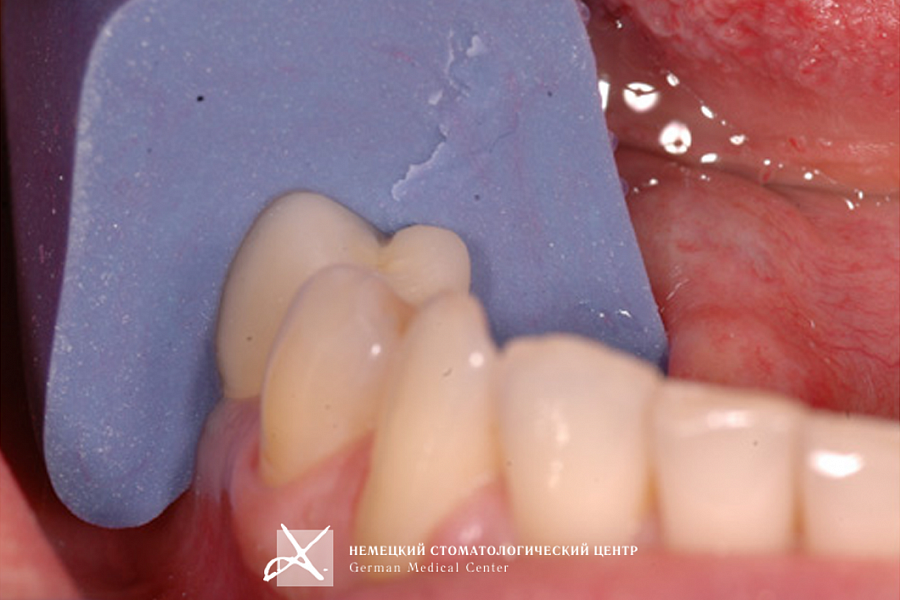

Учитывая тот факт, что диаметр имплантата практически всегда вынужденно меньше диаметра восстанавливаемого зуба в данной анатомической области, чтобы получить максимально эстетический и функциональный результат, было сделано:

- Поэтапное "выстраивание" десневого контура ("кратера прорезывания") с помощью индивидуально моделируемой диагностической промежуточной коронки и индивидуально построенной супраструктуры (абатмента), выполненной из золотосодержащего сплава.

- На индивидуальный абатмент зацементирована эстетическая керамическая коронка.